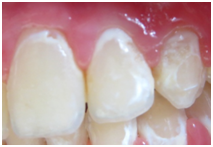

Figure 1 Active lesions (Nyvad classification) sample Classification.

Figure 3A Lucas before tooth mousse use.

Figure 4A Angelica before tooth mousse.